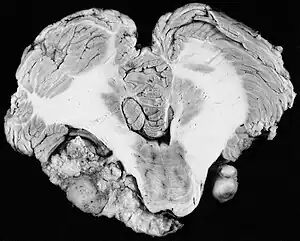

| Bilateral schwannomas in a person with neurofibromatosis 2 | |